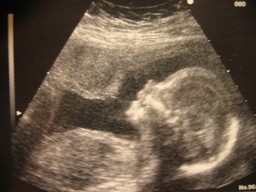

Sikiö kehittyy kohdussa lapsiveden suojassa. Sikiö tarvitsee happea ja ravintoa. Niitä sikiö saa äidiltä napanuoran kautta. Samaa tietä poistuvat sikiön tuottama virtsa ja hiilidioksidi. Sikiön elimet ja aistit kehittyvät nopeasti. Sikiö osaakin jo monia asioita. Sikiö oppii muun muassa tunnistamaan puhujan ja osaa halutessaan potkia jaloillaan.

Kuvasarja sikiön kehittymisestä